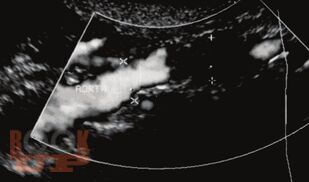

В учебном пособии раскрыты клинические особенности пациентов с окклюзирующими заболеваниями артерий нижних конечностей; представлены клинические и лабораторные методы исследования. Особое внимание уделено медицинской реабилитации пациентов после бедренно-подколенного шунтирования.